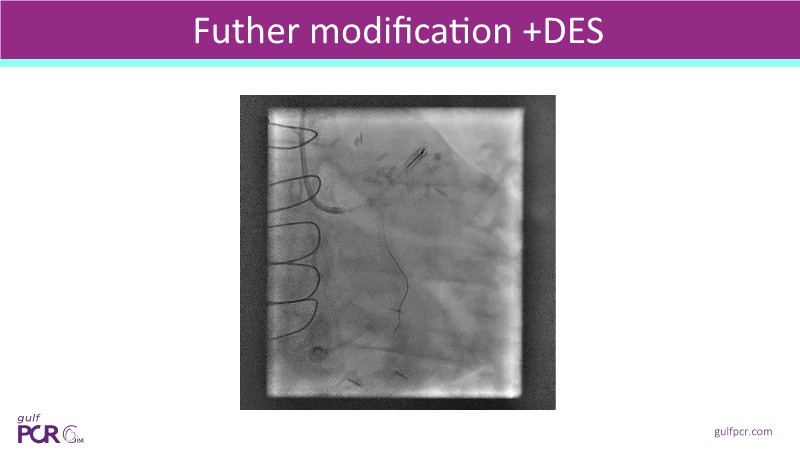

Calcified coronary lesions are a major challenge in PCI. This PCRGulf-GIM 2025 session showcases a complex case with intravascular imaging, highlighting how IVUS 123 guides each step.

From planning the procedure and understanding calcium distribution, to lesion preparation with modern modification tools, and post-PCI assessment to confirm stent expansion and detect complications, this session demonstrates practical, imaging-driven strategies.

Learn how careful preparation and modern techniques improve outcomes in treating severe calcium, calcified nodules, and in-stent restenosis.